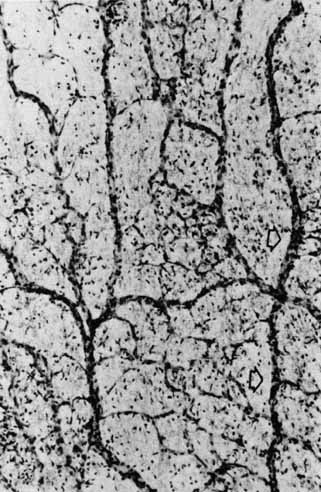

The first detailed study of the anatomy of the retinal vasculature was possible with the advent of the trypsin digest technique. This provided an initial framework for the understanding of retinal vascular physiology. More detailed understanding of the retinal vasculature has been possible recently with progress in whole-mount tissue preparations. Clinical use of fluorescein angiography and newer techniques of vascular flow measurements, e.g., scanning laser Doppler flowmetry, have made possible the correlation between in vivo physiologic vascular changes and previously observed histologic changes in various pathologic entities.